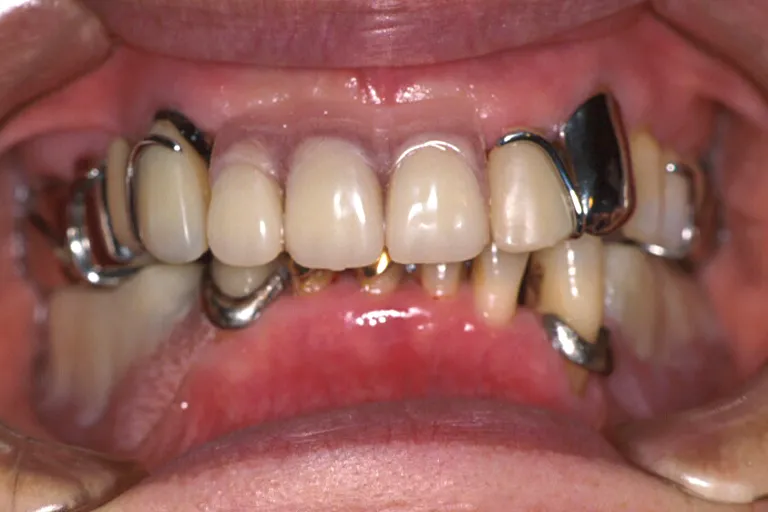

■術前の状態■多くの治療跡があり上顎は大半の歯が失われています総合的に見直して治療する必要があります

■術前の状態■

多くの

治療跡があり

状態が悪い